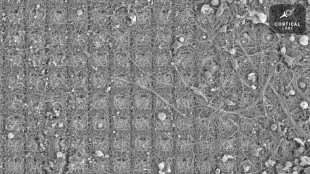

Neuronas de laboratorio aprendieron a jugar un videojuego (estudio)